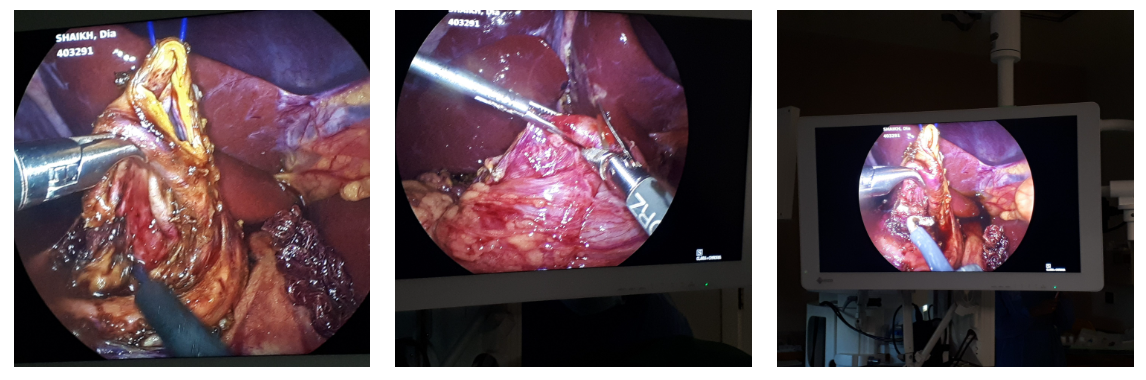

A Fleet of 24 Magnets Were Removed Successfully

Emergency surgical removal of 24 ingested magnets causing multiple intestinal perforations and fistulae in a child.